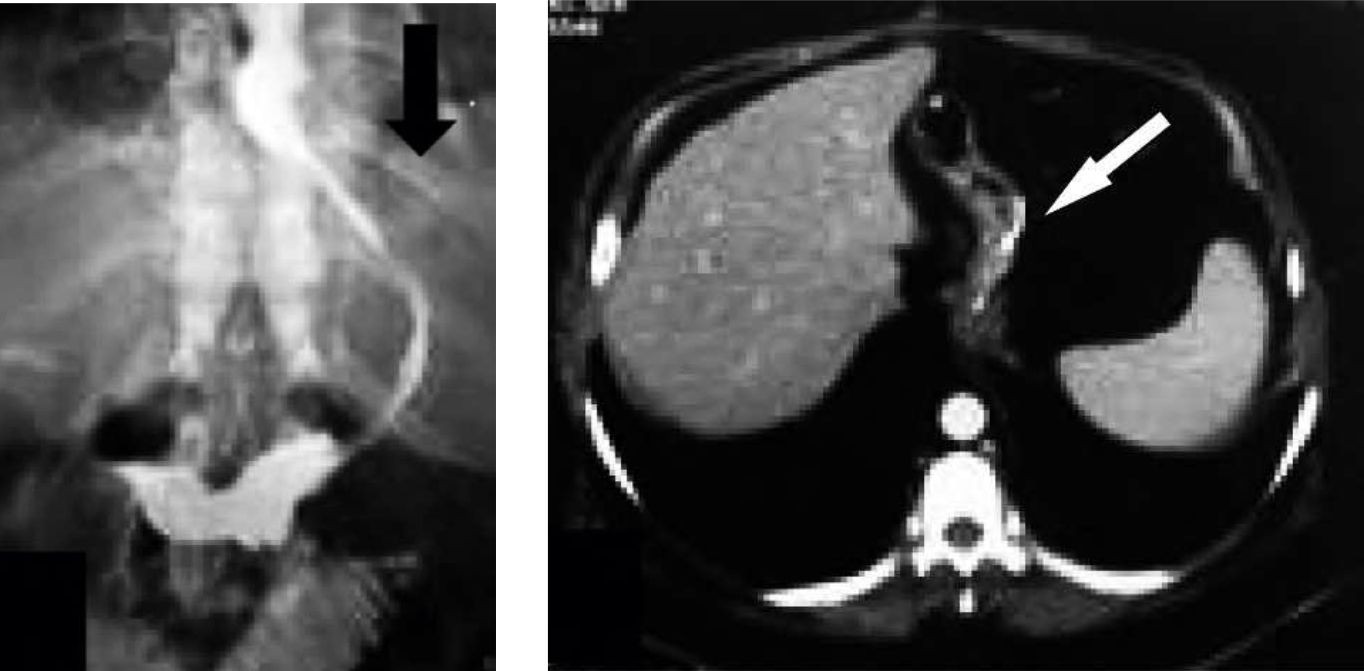

Figura 6

Paciente que al 3er día del postoperatorio refiere dolor abdominal.

Se realiza una TC con contraste i/v que evidencia alteracion de a grasa perigástrica.

EGD del mismo paciente que muestra en la evolución un trayecto fistuloso lateral derecho (flecha fina) con catéter de drenaje (flecha gruesa).(Paciente Nº4)

Figura 7

Paciente cursando postoperatorio mediato que comenzó con dolor abdominal y taquicardia.

a) Corte axial

b) Reconstrucción coronal de TC

con medio de contraste i/v, sin contraste oral observándose un absceso a nivel subfrénico izquierdo (flecha fina) y escaso derrame pleural del mismo lado (flecha gruesa)(Paciente Nº 6)